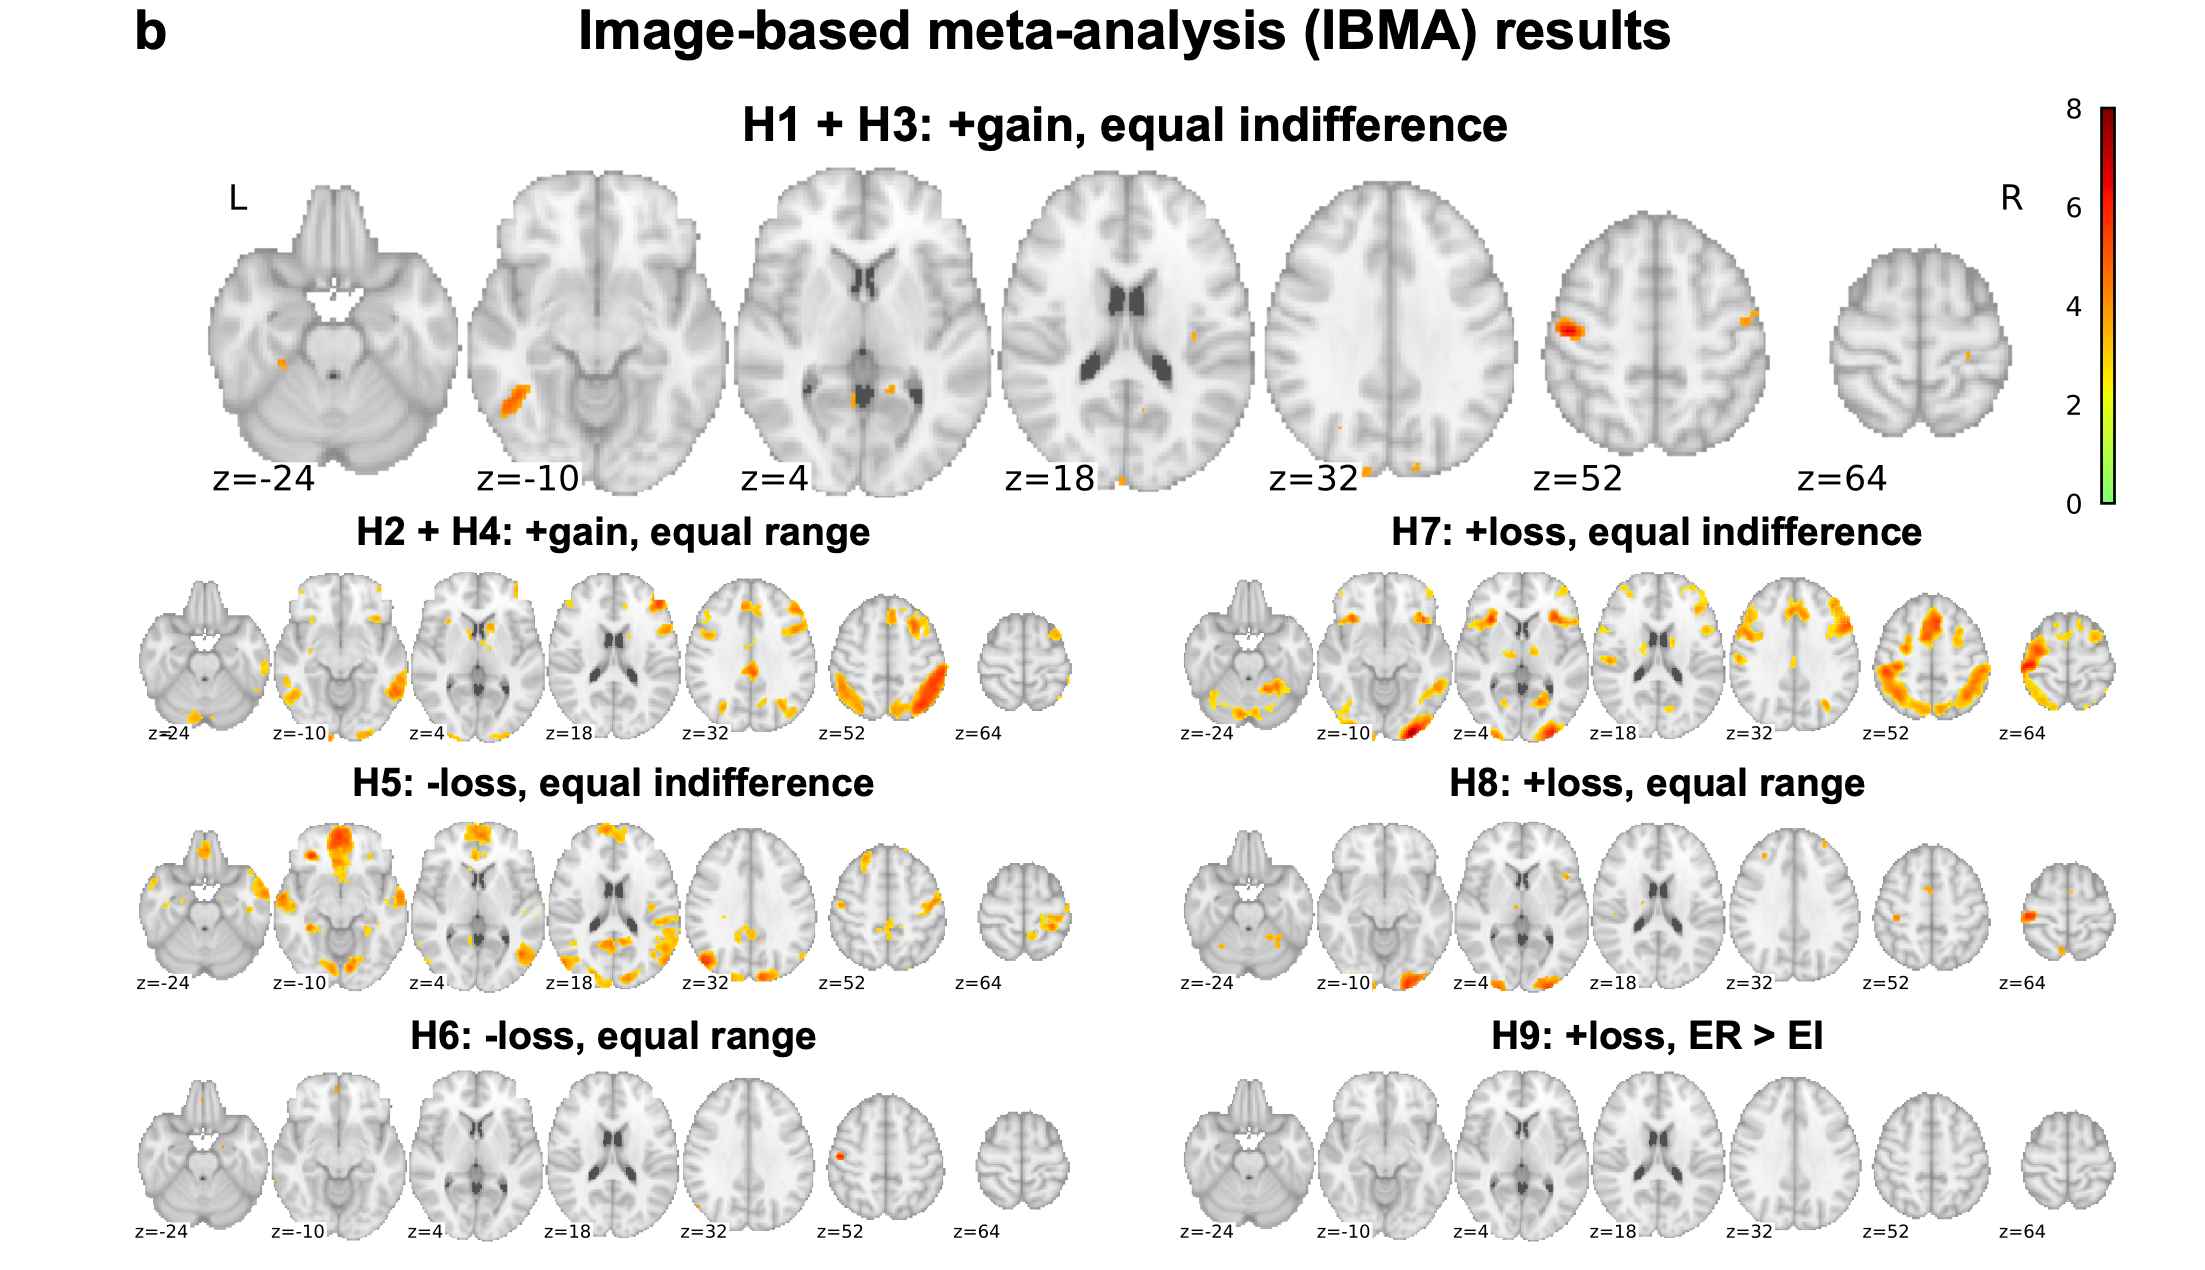

Botvinik-Nezer et al., 2020, Nature

Proportion of teams with activity in each voxel

Maximum overlap for all hypotheses: 76%